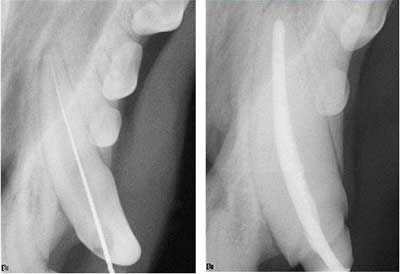

Figure 4: Apical "delta" of a dog canine tooth.

Dog teeth have a different apical anatomy than humans. With humans, we see one, maybe two foramina exit the root at or near the apex. Dogs have a "delta" at the apex that is a dense network of vascular and nerve bundles exiting the tooth (figure 4). This means the final obturation is shorter from the apex than we see for human teeth.

Once the canal is accessed, the procedure is the same: determine the working length to the apex using a K-file (figure 5B), shape the canal using an extended rotary LightSpeed file (Discus Dental), and irrigate with an extended version of the EndoVac (Discus Dental). Figure 6A shows the radiograph of the K-file.

Figure 6A (left): Determining the working length. Figure 6B (right): Final obturation. Note crown prep margins evident in radiograph.

The final obturation is accomplished using a SimpliFill #150 gutta-percha point (Discus Dental) after filling the canal with EndoREZ endodontic canal sealer (Ultradent). Figure 6B shows the final endo fill; you can see the crown prep margins. A nonprecious metal crown was fabricated since this is a service dog (figure 7A). Private owners usually opt for an all-ceramic crown (figure 7B).